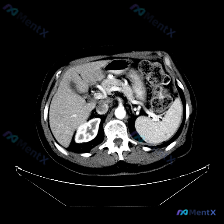

看到一个病例资料挺有意思,整理了一下思路和大家讨论。 用户最初的问题是“图中观察到的特定异常是什么?脾脏病变”,等于先给了一个“存在脾脏病变”的前提。但拿到这张上腹部CT横断面图像(倾向于增强扫描的动脉期或门脉期),仔细看下来,情况其实不太一样。 --- 先看影像层面的客观发现: - 扫描质量与层面...

最近看到一个有意思的影像病例,预设是要讨论「脾脏病变」,但看完影像报告和分析后,发现核心其实是「澄清矛盾」,整理一下思路和大家分享。 --- 先看完整的影像观察结果 这是一份腹部CT横断面的分析: - 实质脏器:肝、胰、脾、肾都大致正常——肝脏密度均匀,胰周脂肪间隙清晰,脾脏形态/大小正常、密度均匀...

今天看到一个有意思的影像读片案例:提问直接预设了“脾脏病变”,但仔细看完提供的资料,发现情况好像不太一样。整理了一下思路,和大家分享。 先看影像资料(客观描述) 这是一张上腹部CT横断面软组织窗影像,报告里的客观表现: - 肝脏:形态尚可,密度基本均匀,未见明确异常高低密度占位,边缘清晰,血管走行正...